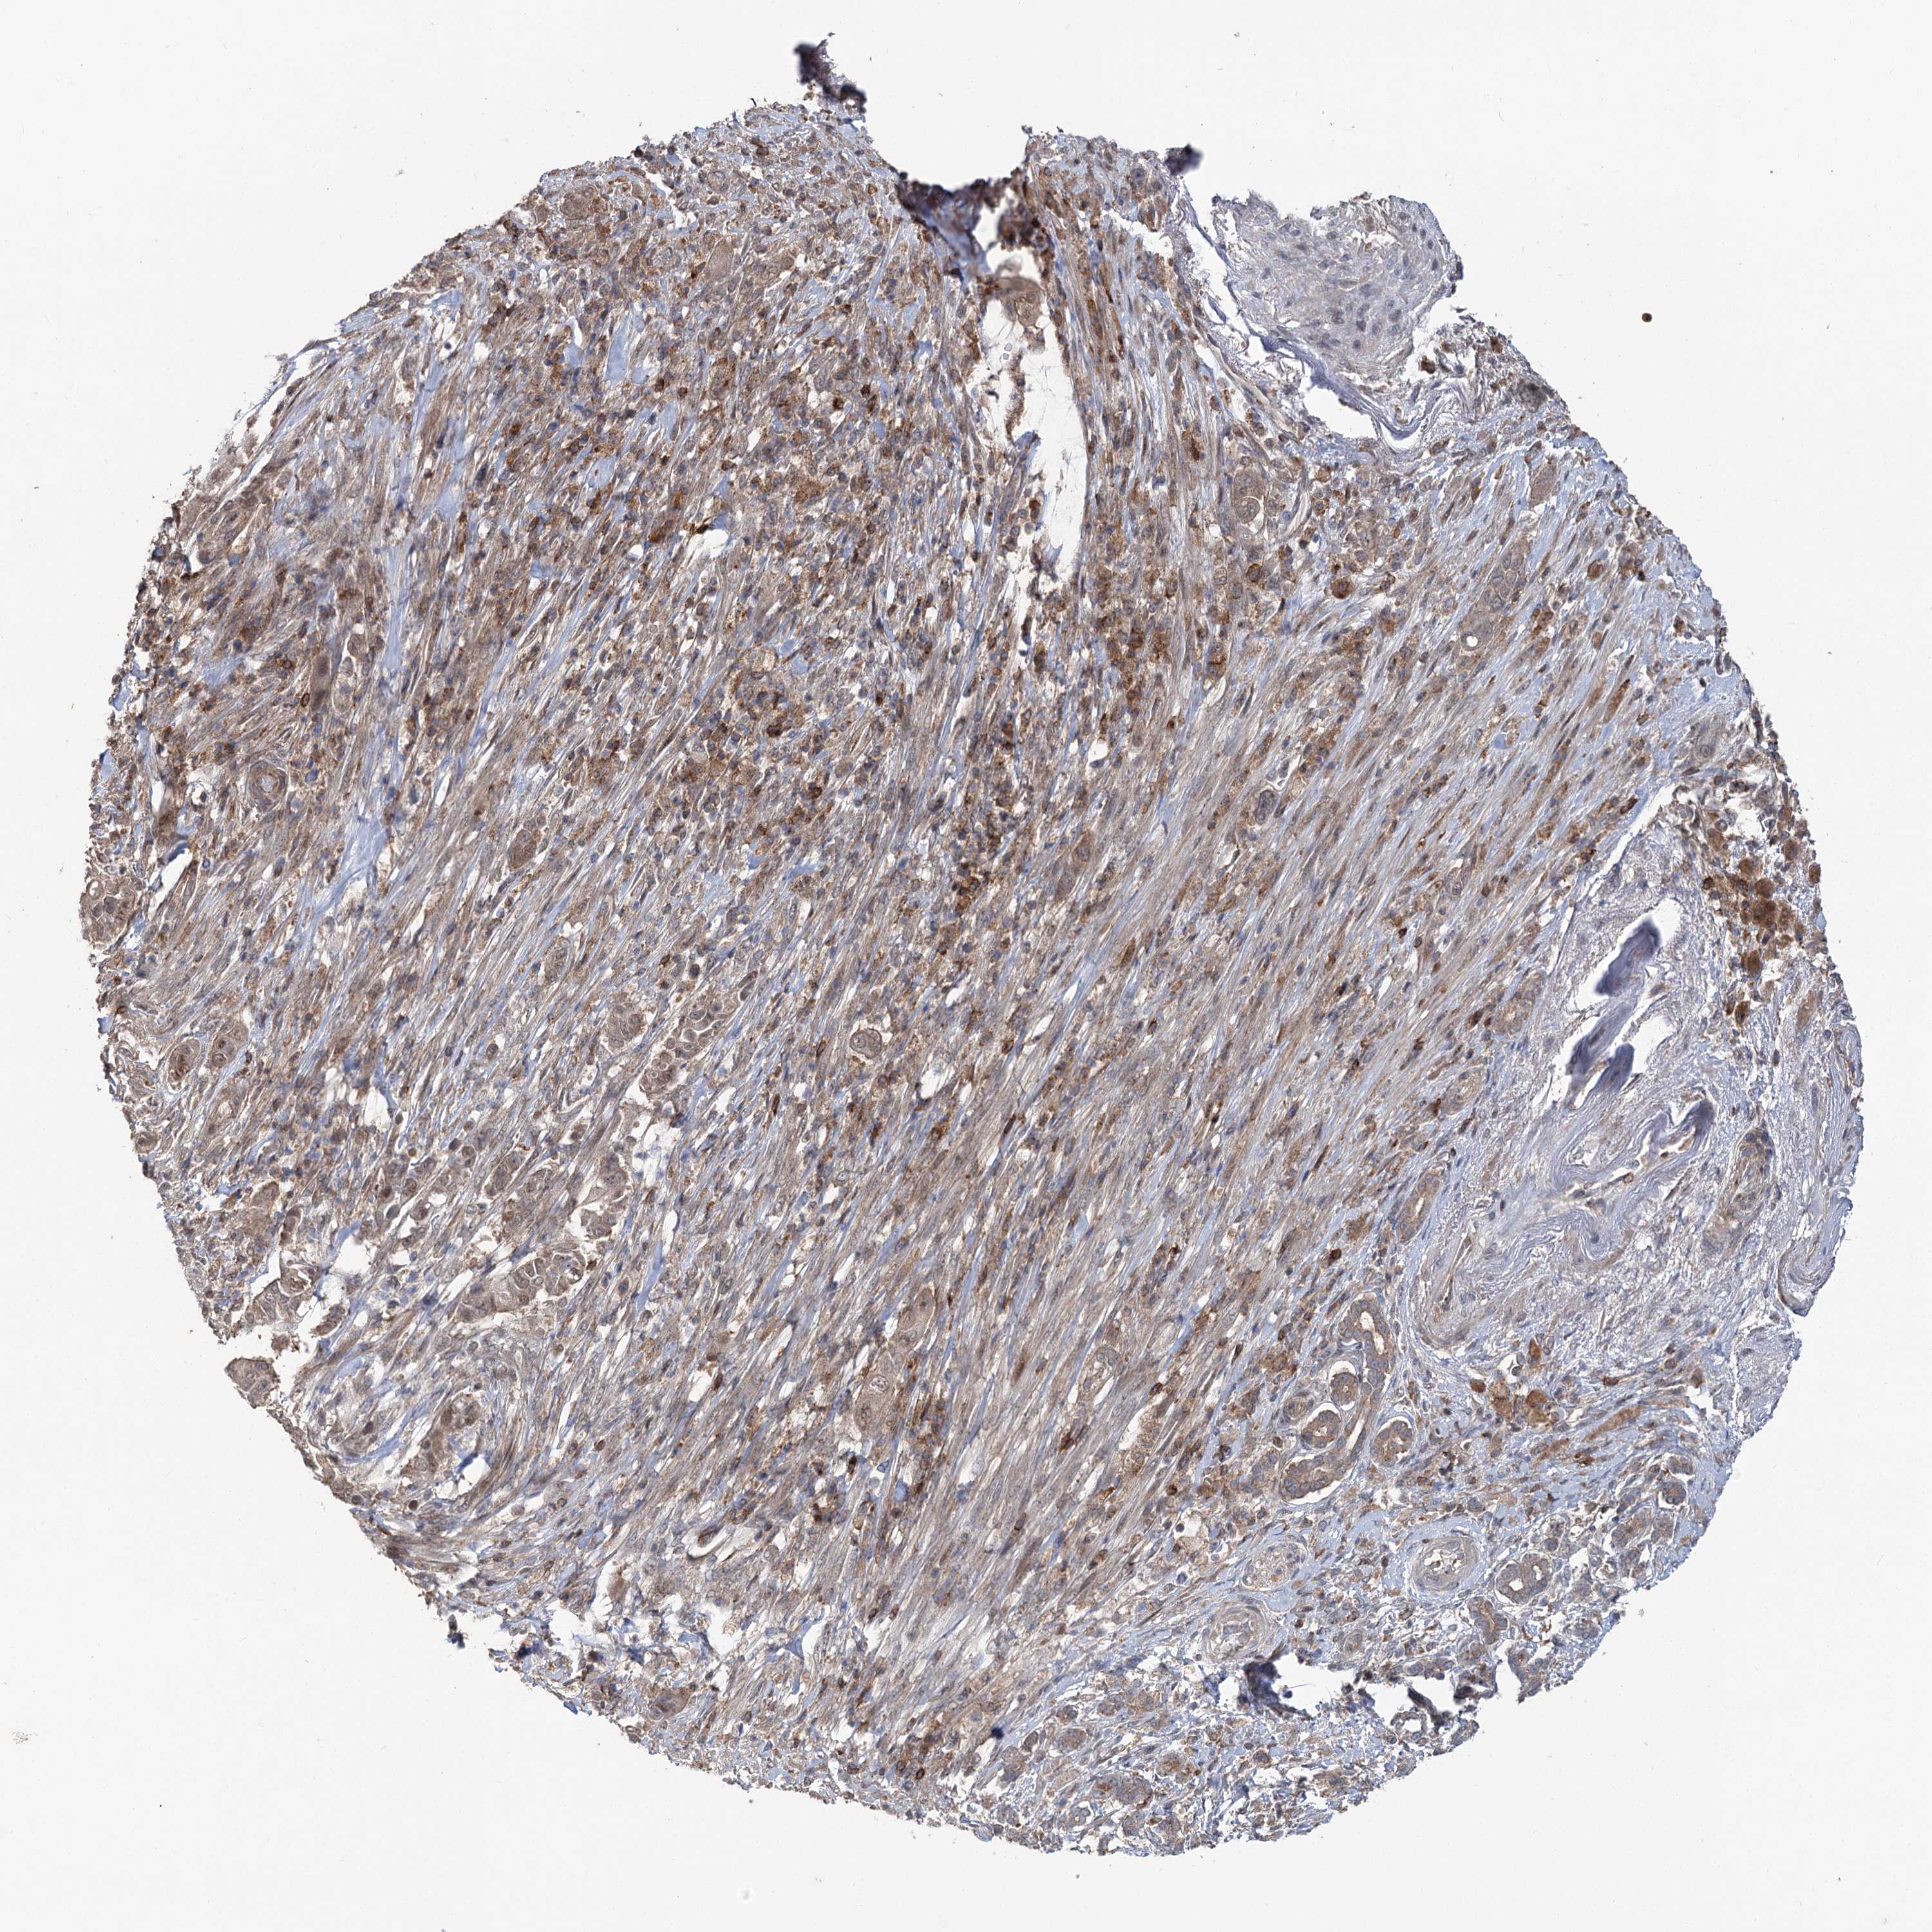

PANCREATIC CANCER - Protein expressioni

A mouse-over function shows sample information and annotation data. Click on an image to view it in a full screen mode. Samples can be filtered based on level of antibody staining by selecting one or several of the following categories: high, medium, low and not detected. The assay and annotation is described here.

Note that samples used for immunohistochemistry by the Human Protein Atlas do not correspond to samples in the TCGA dataset.

Antibody stainingi

Antibody staining in the annotated cell types in the current human tissue is reported as not detected, low, medium, or high, based on conventional immunohistochemistry profiling in selected tissues. This score is based on the combination of the staining intensity and fraction of stained cells.

Each image is clickable and will lead to virtual microscopy that enables deeper exploration of all samples and also displays staining intensity scores, fraction scores and subcellular localization as well as patient and tissue information for each sample.

Antibody HPA038557

Antibody HPA038558

Adenocarcinoma, NOS